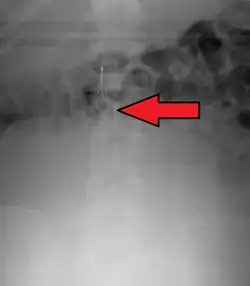

Inferior vena cava filter as seen on plain X ray of the abdomen

Abdominal radiograph shows that one of the legs (arrows) of the IVC filter is pointed away from the expected IVC lumen.